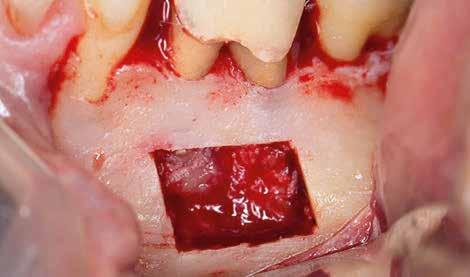

A beavatkozás során helyi érzéstelenítésben teljes vastagságú mucoperiostealis lebenyt képeztünk, és a sablon segítségével bejelöltük a preparálandó csontablak határait. Az ablak széleinek megfelelően Piezotome CUBE LED kézi-darabbal (ACTEON) a kortikális teljes vastagságában vágást ejtettünk, majd az így kapott csontlemezt (ablakot) eltávolítottuk (1. e–h. ábra), és ezt követően steril fiziológiás sóoldatba helyeztük. A rezekció elvégzését követően (1. i. ábra) a mezialis csatornákat ultrahangos eszközök segítségével (NSK) retrográd irányból preparáltuk, majd az így kialakított mélyedésbe retrográd gyökértömést készítettünk. A tömés anyagául az EndoSequence BC RRM Fast Set Putty-t (Brasseler) választottuk. A tömés elkészítését követően a csontablakot visszaillesztettük, és a stabilizálása érdekében a vágásoknak megfelelően kialakult résekbe kollagén szivacsokat (Collagen Tape, Zimmer Biomet) helyeztünk (1. j-k. ábra). A lebenyt 6/0-s Prolene varratokkal (Corpaul) rögzítettük.

A kétéves kontroll során elvégzett klinikai és radiológiai vizsgálat (CBCT-felvétel) a periapicalis elváltozások megszűnését és a corticalis csontállomány tünet- és szövődménymentes gyógyulását